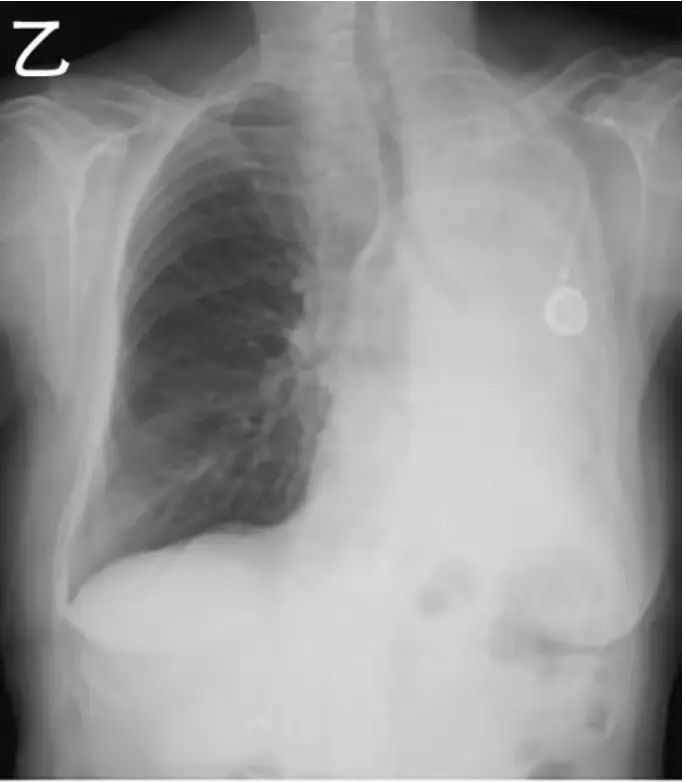

甲、乙兩位病人都主訴呼吸喘及左胸不適,胸部 X 光檢查如圖 (九)。關於是否適合進行左胸胸管引流做為緩解病人症狀的處置決策,下列何者最適當?

- 乙:左側幾近全肺呈高密度陰影,左側氣管與心膈向同側偏移,顯示左肺組織體積明顯減少,為左側complete atelectasis(肺不張)所致,並非胸膜腔積氣或積液。

- 選項A(甲、乙皆適合):錯誤。甲為肺實質內巨大肺泡,非胸膜腔積氣;乙為肺不張,非需胸管處理之胸膜腔病變。

- 選項C(甲不適合、乙適合):錯誤。乙為肺不張,胸管無助恢復肺擴張。

- 選項D(甲、乙皆不適合):正確。兩者病變均不在胸膜腔中,無法藉胸管緩解。